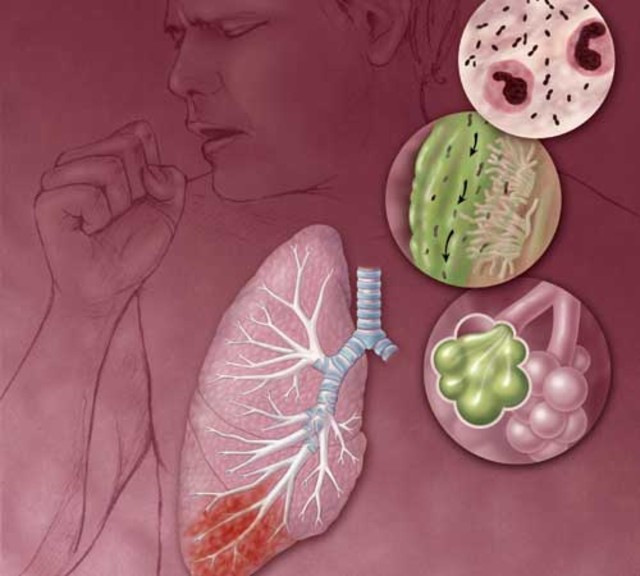

Фотографии бактерий, вызывающих бактериальные пневмонии у животных

Раздел: Другие животные